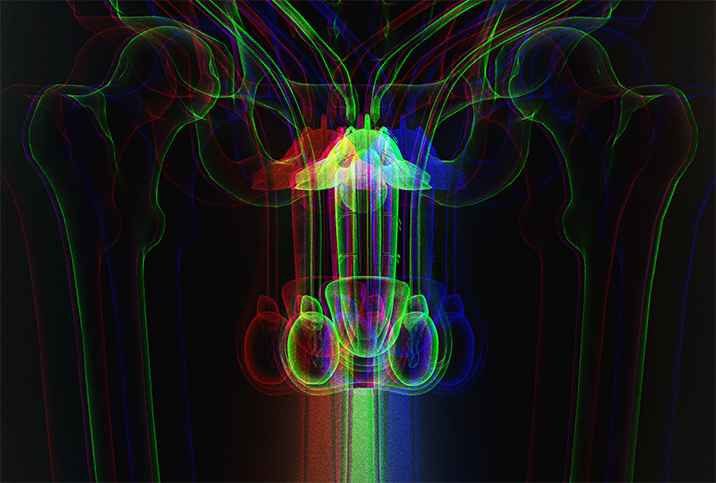

Get a Grip on Testicular Cancer and How to Detect It

Symptoms of testicular cancer

The most common symptom of testicular cancer is a painless lump or bump on the testicle, according to Samuel Haywood, M.D., a urologic oncologist at the Cleveland Clinic who encourages anyone who feels an abnormality to have their doctor take a look.

In general, a new lump is the way testicular cancer presents for the first time, and, typically, the lump will appear on one testicle—it's relatively rare for cancer to affect both testicles.

While the lump is usually painless, some men experience pain or tenderness in the testicle or scrotum. Dull pain in the abdomen or groin area is another potential symptom of testicular cancer, said Kristian Stensland, M.D., a clinical instructor in the Urology Department at the University of Michigan. These symptoms don't automatically indicate a tumor or cancer, but you'll want to get them checked out by a doctor.

Monthly self-exams

The Testicular Cancer Awareness Foundation provides the following four-step process for a testicular self-exam during or after a warm shower:

- Cup one testicle at a time using both hands.

- Roll the testicle between your thumb and fingers, using slight pressure.

- Get a feel for your spermatic cord and epididymis tube, which connect on the backside of the testicle.

- Feel for lumps or changes in size or consistency.

Conditions with similar symptoms

Testicular cancer shares some symptoms with epididymitis, an infection of the epididymis, the storage tube for sperm situated at the back of each testicle. Epididymitis often causes pain and enlargement of the testicles or swelling in the scrotum from inflammation. The testicles may feel hot to the touch, and potential urinary problems include pain during urination or discharge.